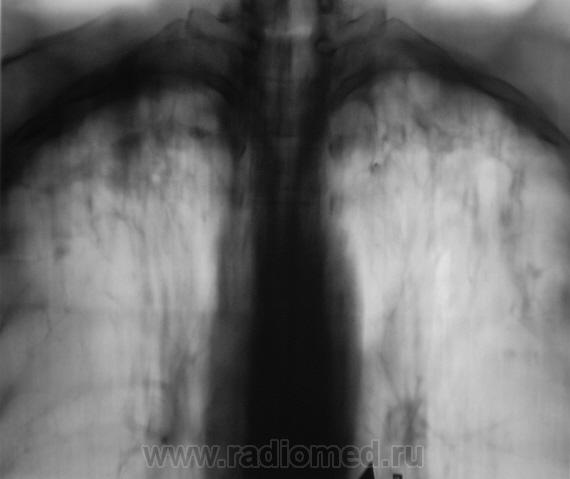

Пациент получает "специфическое лечение". Прошел год.

Пациент направлен на плановое рентгенологическое исследование.

В верхних отделах инфильтрация уменьшилась, очаги уплотняются. А на прицельных снимках нижней доли слева об этом пока говорить рано (об очагах). А что клинически, лабораторные данные?